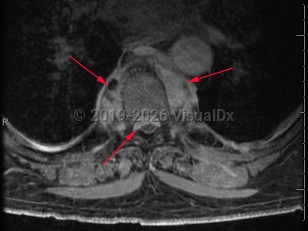

Paraspinal abscess is a collection of pus located around the spinal cord. This is usually seen as a complication of vertebral osteomyelitis and discitis (diskitis) but may be related to hematogenous seeding during bloodstream infection. Epidural catheters and injections may lead to direct inoculation of the epidural space. Frequently, the location of the abscess is in the epidural space.

Patients may have acute (develops over hours) or subacute (develops over weeks to months) back pain. Fever may or may not be present. As the abscess forms, patients typically have focal and severe back pain. As the size of the abscess increases, it may impinge on the spinal cord, leading to signs of spinal cord compression, including motor weakness and sensory deficits. Untreated, the patient's neurologic symptoms can worsen to the point of irreversible paralysis.